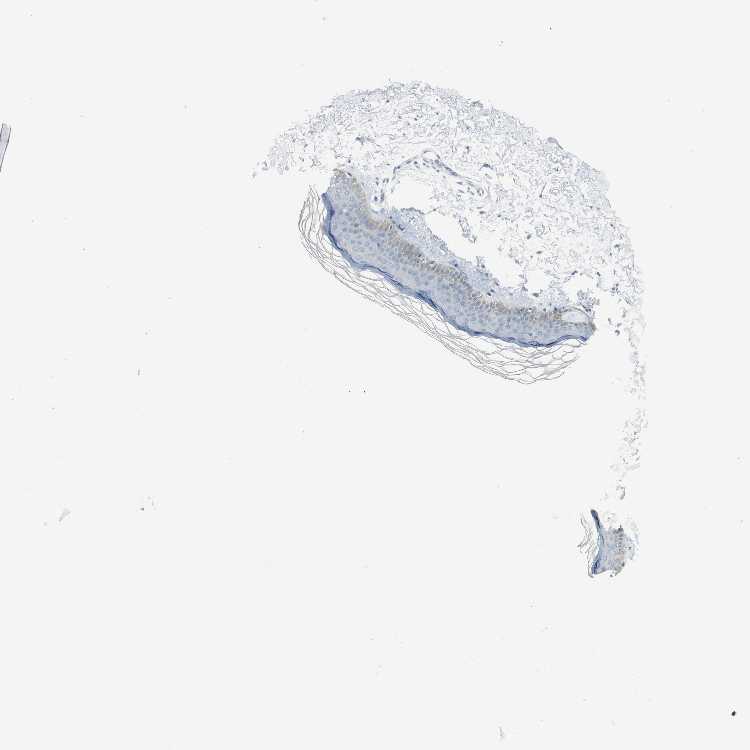

SKIN 2 - Antibody stainingi

Antibody staining in the annotated cell types in the current human tissue is reported as not detected, low, medium, or high, based on conventional immunohistochemistry profiling in selected tissues. This score is based on the combination of the staining intensity and fraction of stained cells.

Each image is clickable and will lead to virtual microscopy that enables deeper exploration of all samples and also displays staining intensity scores, fraction scores and subcellular localization as well as patient and tissue information for each sample.

Antibody HPA005899Antibody HPA005914

Epidermal cells LowNot detected